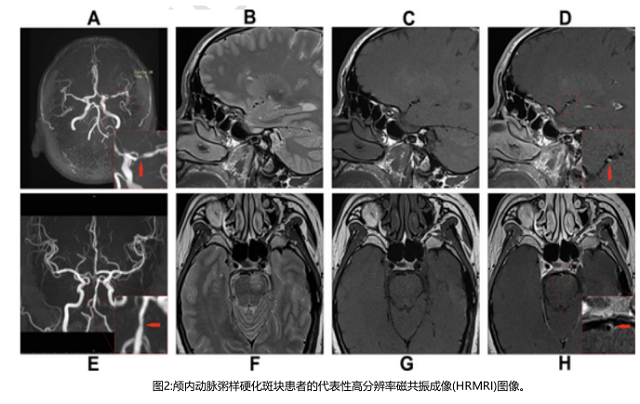

病變部位定義為由MCA動(dòng)脈粥樣硬化病變引起的管腔狹窄最嚴(yán)重的水平(圖2)。通過血管-腦脊液界面自動(dòng)計(jì)算血管面積(VA)。管腔面積(LA)由血管-血液界面計(jì)算。選擇斑塊最厚的切片來測(cè)量直徑。壁面積(WA)計(jì)算為血管面積減去管腔面積。斑塊面積為病變部位的WA減去參考部位的WA。斑塊負(fù)擔(dān)計(jì)算為斑塊面積/病變部位血管面積× 100%。狹窄率公式為(病變部位1-LA /參考部位)× 100%。重構(gòu)指數(shù)(RI)是指病變部位血管面積與參考部位血管面積之比。陽性重構(gòu)(PR)定義為RI > 1.05;負(fù)重構(gòu)(NR)定義為RI < 0.95;中度重構(gòu)定義為RI在0.95 ~ 1.05之間。